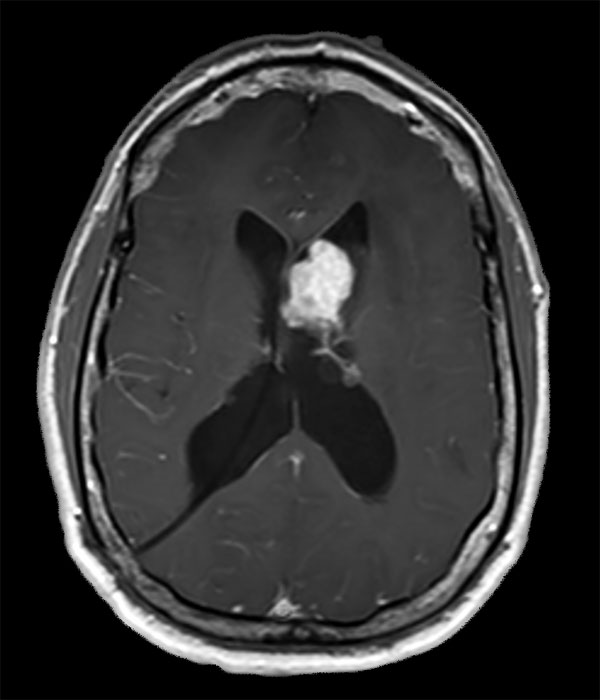

Axial T1W SE (with gado)